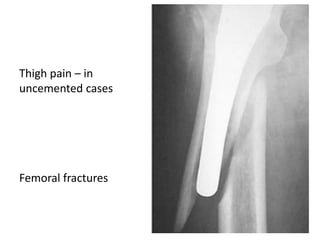

Thigh pain – in

uncemented cases

Femoral fractures

Thigh pain –in uncemented cases Femoral fractures